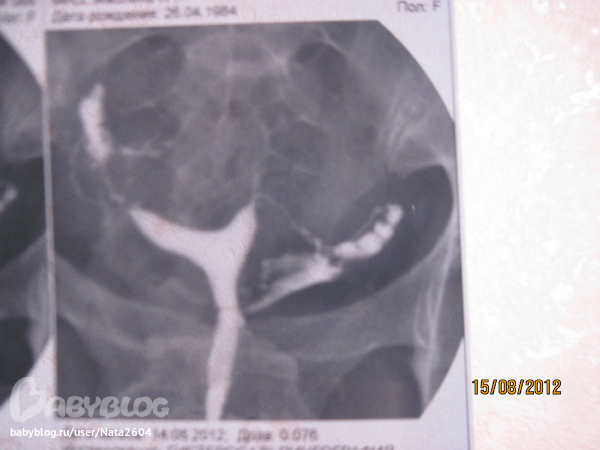

А вот заключение: Проходимость маточных труб сохранена. НО протоколе обследования есть еще одна штучка: "Левая маточная труба контрастируется по типу "чёток" в ампулярном отделе".

А вот и снимки, правда получились на нашу мыльницу не очень, не так ярко

а по типу "четок", это видно на Вашем третьем снимке, словно шарики/четки в трубе. Если смотреть на снимок, то в правой трубе. Я думаю это ничего плохого не значит.... глвное, что трубы проходимы.

Мне когда вливали раствор, я прям чувствовала, как жидкость по трубам проходит. Звонила вчера своей знакомой Г, она сказала что где эти чётки, там есть спайки, а то что у меня и на следующий день болел живот, как она мне объяснила, жидкость эта выходит в брюшную полость (когда делают контрольный снимок) и так организм реагирует на этот раствор, главное чтоб не было температуры и не началось воспаление. К своей Г на прием только в конце августа. Посмотрим что скажет, может на лапару пошлет.